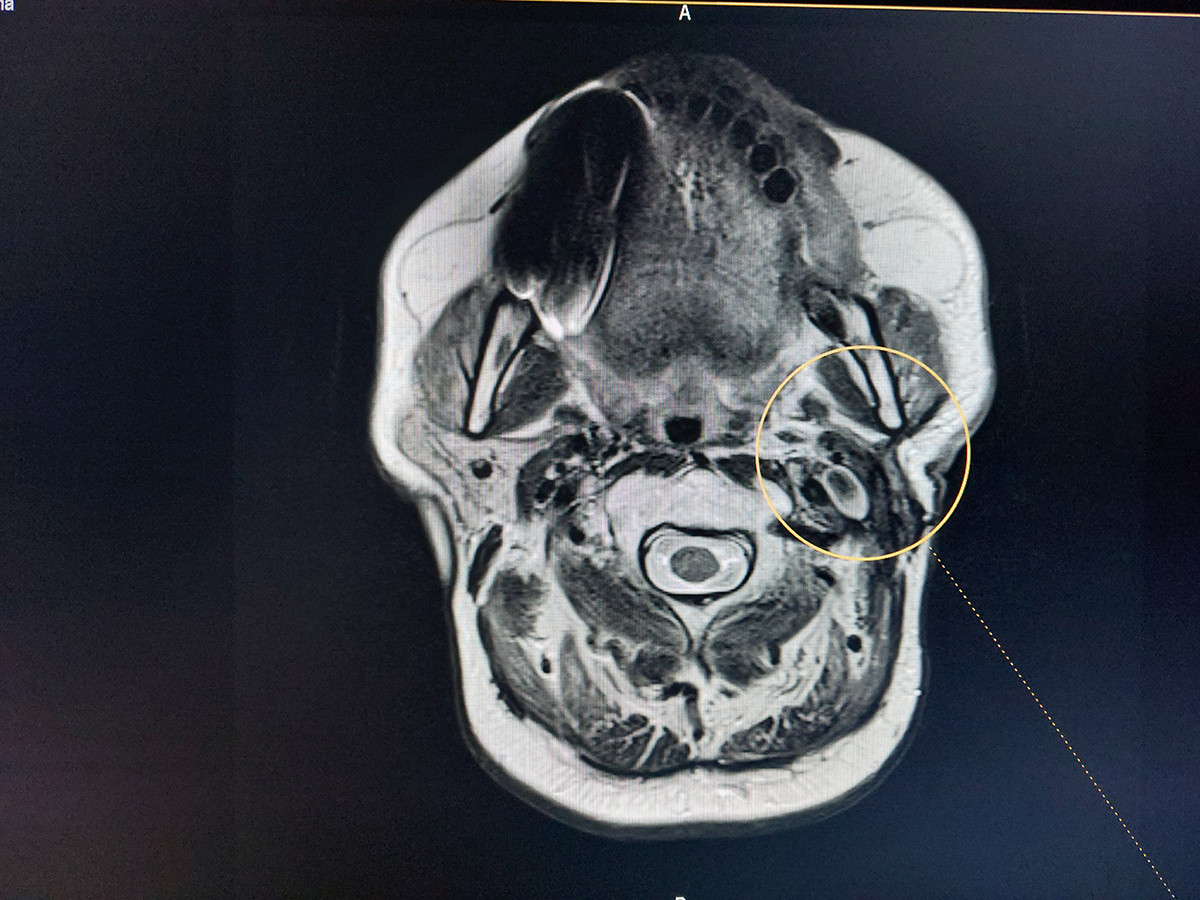

Նախքան «Նաիրի» ԲԿ դիմելը պացիենտի մոտ ախտորոշվել է հարականջային թքագեղձի ադենոմա։ «Նաիրի» բժշկական կենտրոնում կատարվել է թքագեղձի մագնիսա-ռեզոնանսային տոմոգրաֆիա, և պարզվել, որ ավելի քան 5 տարի գոյություն ունեցող թքագեղձի ադենոմայի ներսում առկա է մոտավորապես 1 սմ պինդ գոյացություն։ Իրականացվել է հայտնաբերված պինդ գոյացության պունկցիոն բիոպսիա և, արդյունքում, ախտորոշվել է ուռուցք` թքագեղձի ադենոկարցինոմա: Սա այն դասական դեպքերից է, թե ինչպես կարող է բարորակ գոյացությունը, տարիներ շարունակ անտեսելու, չբուժելու արդյունքում վերաճել չարորակ ուռուցքի։

Քանի որ գոյացությունը մեծ էր և շատ մոտ էր գտնվում դիմային նյարդին (դիմային նյարդը նյարդավորում է դեմքի միմիկայի բոլոր մկանները), կատարվեց ամբողջական հեռացում: Մանրադիտակի կիրառման պայմաններում դիմային նյարդն ամբողջապես պահպանվեց։ Երկու-երեք ամիսների ընթացքում դեմքի միմիկայի բոլոր մկանները վերականգնվեցին՝ թե՛ ֆունկցիոնալ, թե՛ էսթետիկ առումով, ինչը թույլ տվեց մեր պացիենտին շարունակել իր մասնագիտական գործունեությունը։